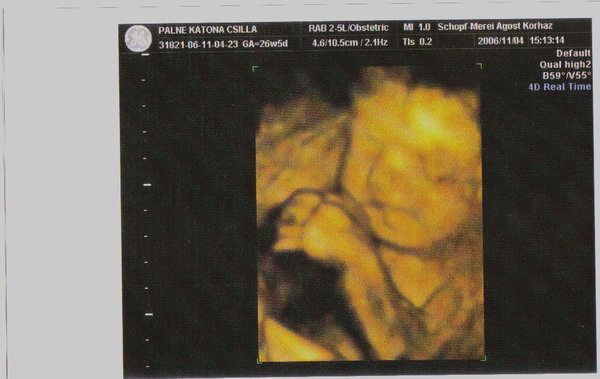

Uh-val az a helyzet, hogy nálunk kizárólag a megyei kórházban készült uh-t fogadják el hivatalosnak. Tehát, rá vagyok kényszerülve. Persze a 16. héten voltunk a magándokimnál "nemhivatalos" uh-n, és az nagy élmény volt. Azt azonban nem szeretném, hogy csak az én lelkecském miatt kétszer zaklassuk a babát (egy uh a rendelőben a mamának, egy uh a kórházban a kiskönyvbe). Lehet, azt mondjátok, hülye vagyok, és tudom, hogy semmi baja nem lesz, de akkor is úgy érzem, hogy utálja a gyerek. A megnyugtatásunk miatt azért még v.szeg elmegyünk egyszer pluszban a 24. hét körül.

De akkor már inkább 4D-re.